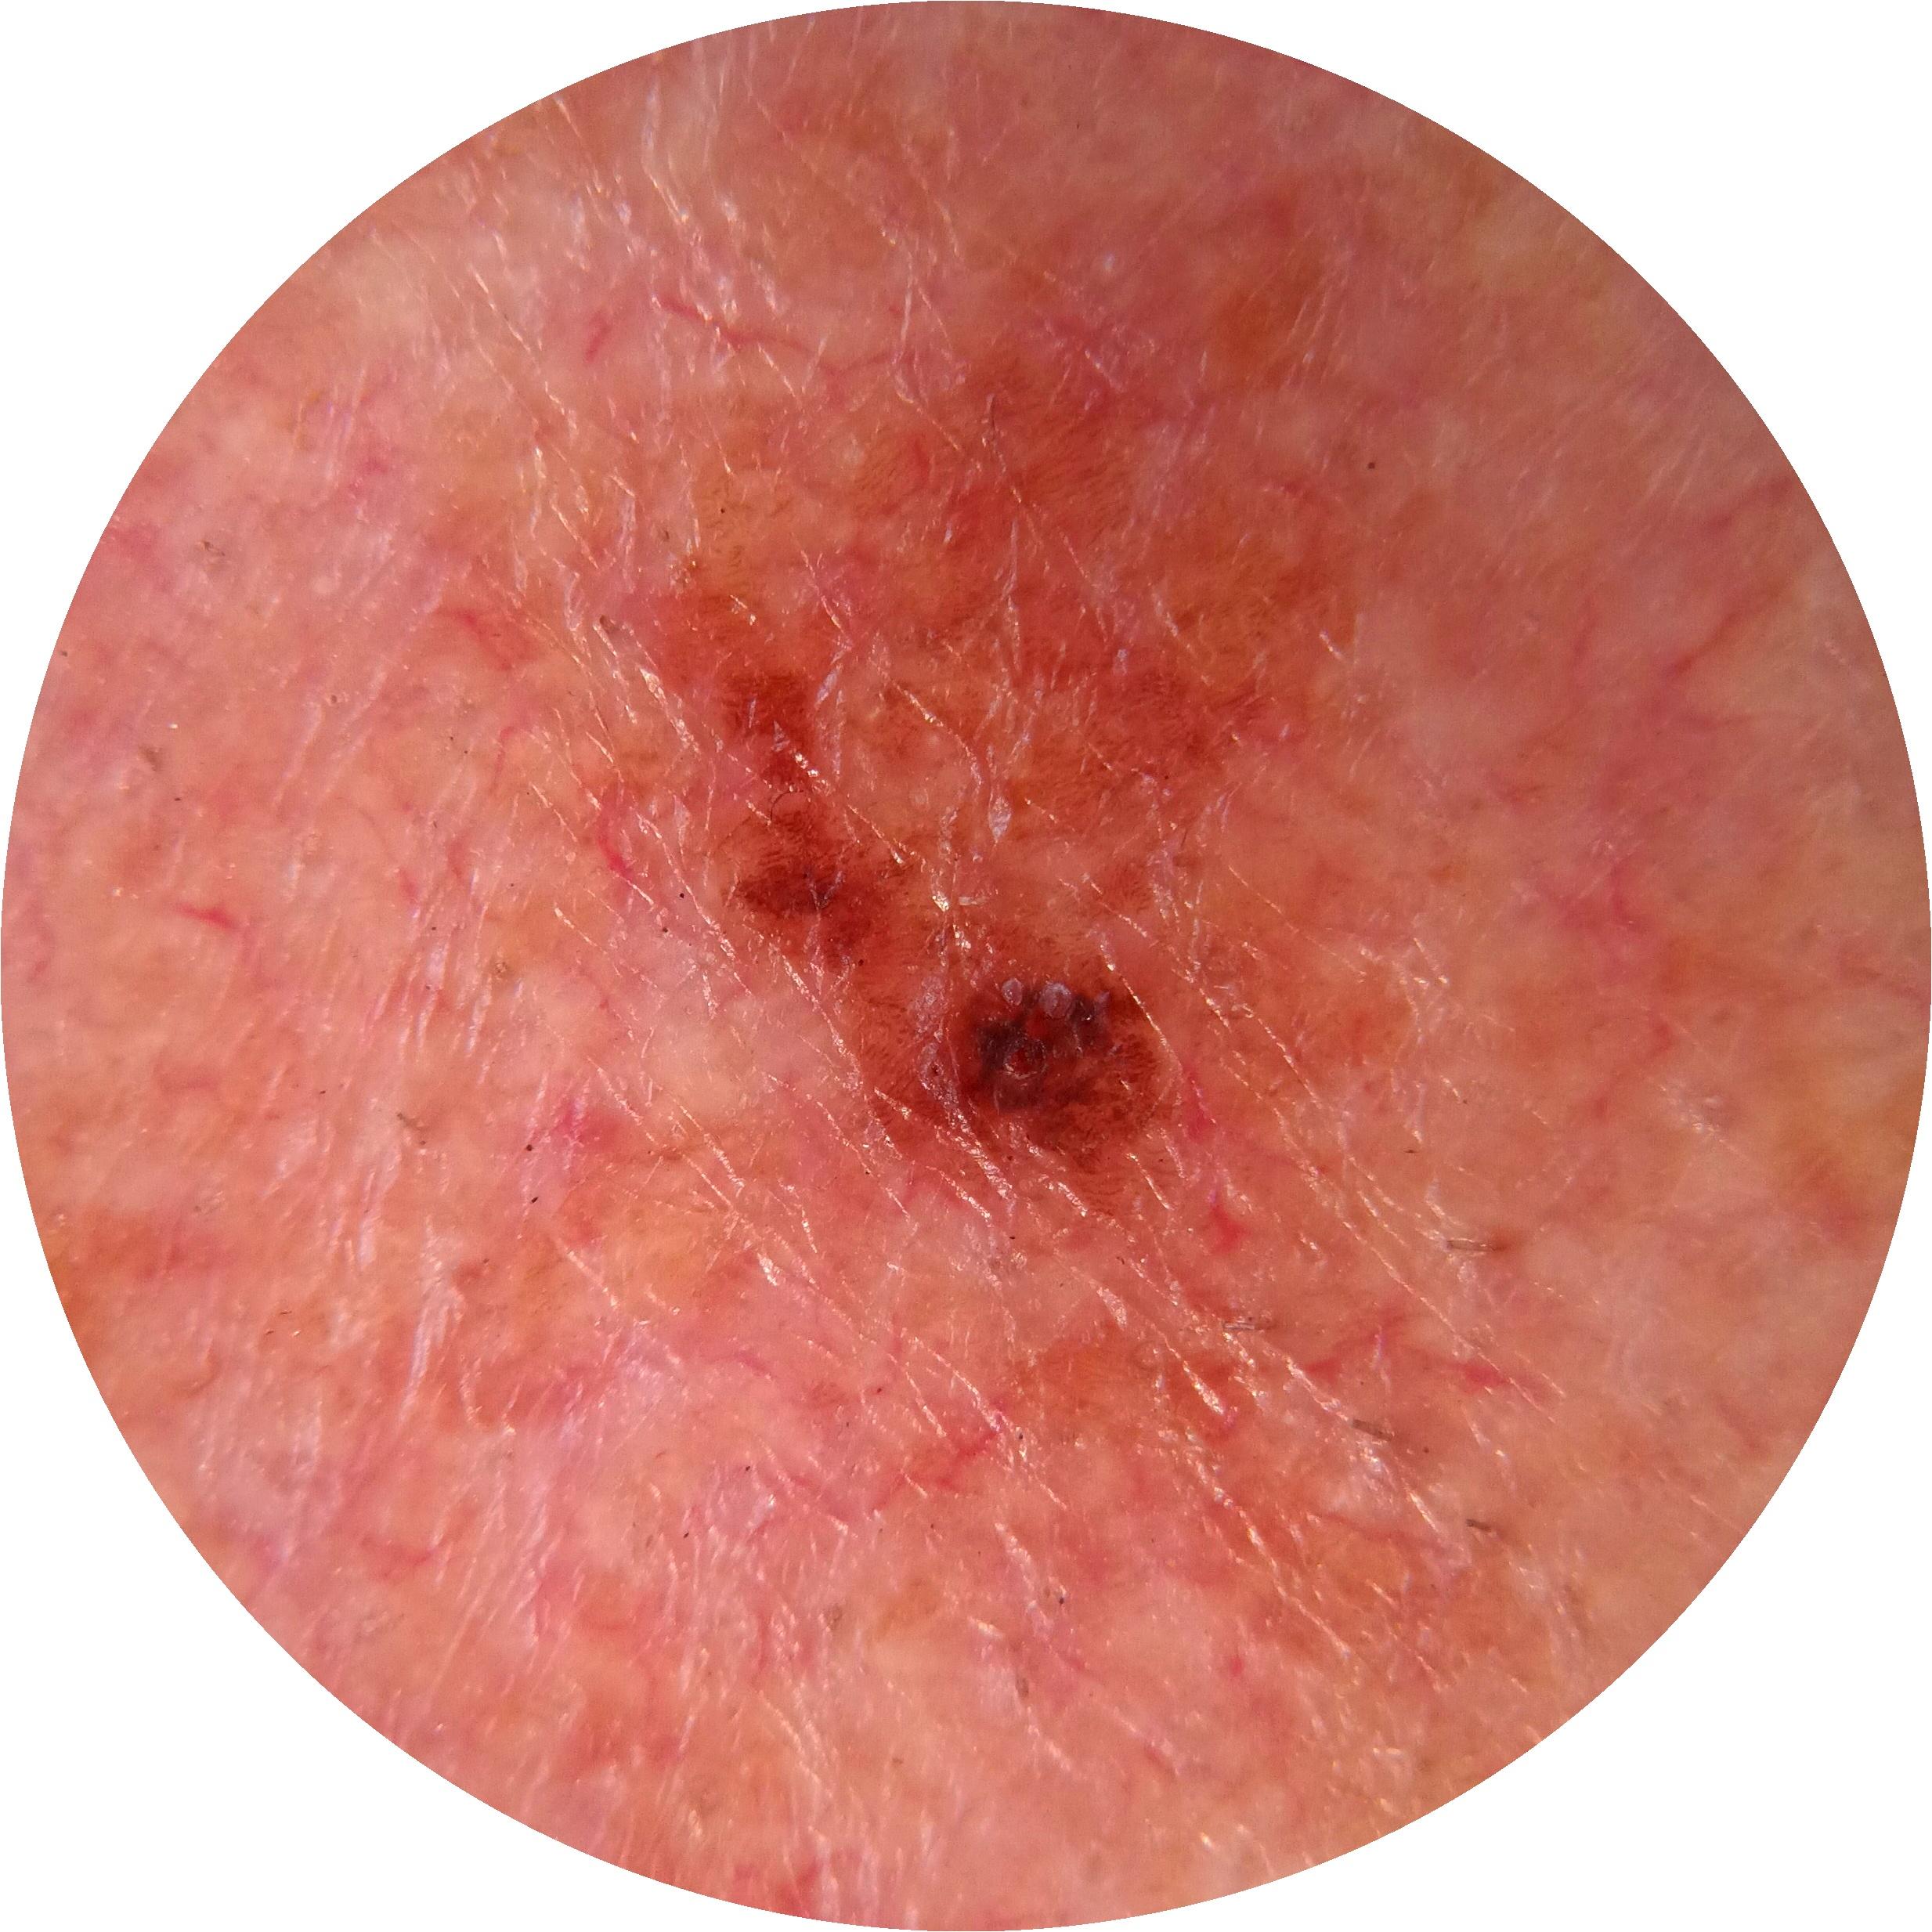

ISIC_7740426

1172 x 1172

Clinical

Field Value

acquisition_day 278

age_approx 65

anatom_site_1 Head and neck

anatom_site_general head/neck

diagnosis_1 Benign

family_hx_mm False

image_manipulation instrument only

image_type dermoscopic

lesion_id IL_9049639

patient_id IP_3152710

personal_hx_mm True

sex male